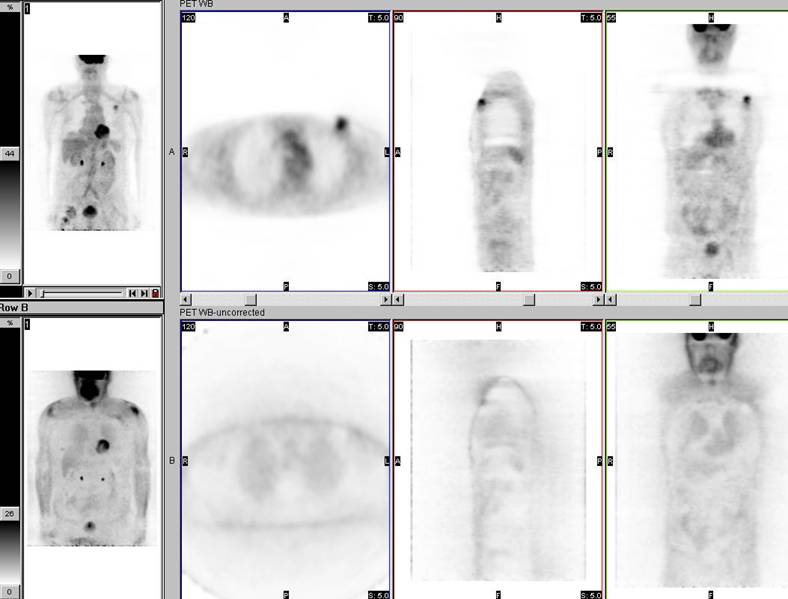

There is intense activity in the left upper chest wall which correlates exactly in location with a metallic density pacemaker.

Because of the significantly higher density of metallic hardware compared to normal body tissues, the PET attenuation correction process "overcorrects" the PET images, essentially "adding in" activity to the tissues containing the hardware. This is because photons originating in these locations (if there were any) would be markedly attenuated by the metal. Of course, in the exact location of the hardware the artifactual activity "added in" does not pose a problem because it can be attributed to the hardware itself by close inspection of the CT data. However, the activity artifactually "added in" can include tissues closely approximated to hardware (such as muscles or lymph nodes) and this can pose a diagnostic dilemma. Therefore, the non-attenuation-corrected data should always be inspected in addition to the attenuation-corrected data. This will often elucidate whether there is any truly increased activity located within tissues adjacent to hardware. However, in some cases artifacts related to hardware preclude definitive evaluation of activity within adjacent tissues and other means of assessment are needed.

The non-attenuation-corrected data shown in the bottom row confirms that there is actually no increased activity in the left upper chest wall, as was apparent on the attenuation-corrected data shown in the top row. The attenuation correction process resulted in artifactually increased activity in the region of the metallic density pacemaker.